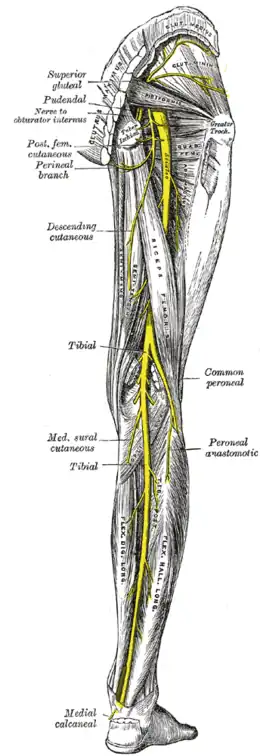

Coupe sagittale du bassin montrant le plexus sacré. Nerfs de la face postérieure du membre inférieur.

Nerfs de la face postérieure du membre inférieur.

Variation

Dans environ 80% de la population, le nerf sciatique passe sous le muscle piriforme. Chez 17 % des personnes, le nerf sciatique traverse le muscle piriforme. Il existe d'autres variations plus rares.

Du fait de la proximité du nerf sciatique avec le muscle piriforme, voire son passage à travers ce muscle, sa sollicitation excessive peut entraîner une inflammation du nerf. Son surmenage peut advenir dans certains sports (course à pied, cyclisme, ...) ou survenir lors d'une mauvaise posture récurrente (mauvais siège et mauvais appui fessier). Ceci peut avoir pour conséquence l'apparition d'un syndrome de type sciatique appelé syndrome du piriforme.